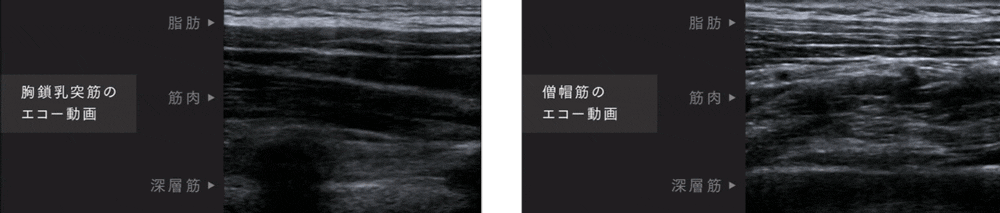

低周波機能

最大限の効果を引き出す独自のテクノロジー

MYTREX独自の理論で周波数とパルス波を組み合わせた低周波テクノロジー「NNRパルス」搭載。

チクチク感を軽減し、筋肉を刺激しながら痛みを緩和。

筋肉を効率的に収縮することで、首・肩まわりの血行を促進し、コリや痛みを緩和します。